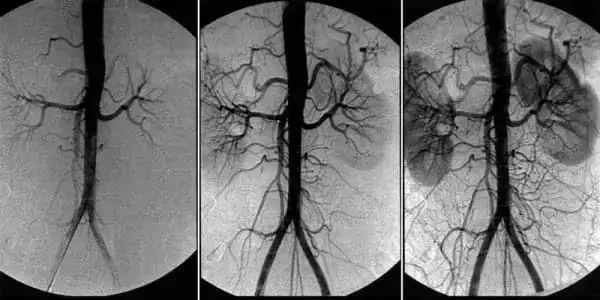

Ангиодистония сосудов головного мозга – это патологическое состояние, при котором нарушается тонус сосудов и нормальное кровообращение в тканях головного мозга. В этой статье вы сможете прочитать про её причины, механизмы и симптомы, при которых пора бить тревогу. А также про грозные осложнения этого коварного заболевания и про современный подход к лечению, доступный каждому.

В основе лечения кровообращения сосудов головного мозга лежит очищение сосудов всего организма от накопленных загрязнений. Холестериновых бляшек, тромбов и кальциевой извести.